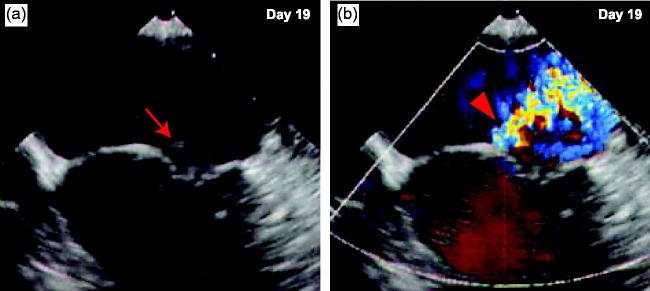

Recent reports suggest that can cause infective endocarditis (IE). However, no data are available regarding infectious intracranial aneurysm (IIA) following endocarditis. Endovascular coiling is a challenging approach for the treatment of IIA. We describe the case of a 63-year-old woman who suddenly developed aphasia and dysarthria following an acute cerebral infarction in her left insular and temporal cortex. After a total hysterectomy at the age of 39, the patient had suffered from recurrent bacterial pyomyositis in her legs. At admission, there was no evidence of cerebral aneurysm, as assessed by magnetic resonance angiography, and no vegetation, as assessed by transesophageal echocardiography (TEE), resulting in an incorrect diagnosis. However, subarachnoid hemorrhage and development of cerebral aneurysm in the left middle cerebral artery occurred within 1 week of hospitalization. Continuous positive blood culture results and a second TEE finally revealed that IE was caused by Coil embolization of the IIA was successful on day 26 after symptom onset; after this procedure, the patient began to recover. This case demonstrates that -induced endocarditis can cause IIA. Endovascular coiling is a potentially effective approach to treat IIA.

最近有报道称 可能导致感染性心内膜炎(IE)。然而,关于 心内膜炎后感染性颅内动脉瘤(IIA),目前尚无数据。血管内线圈栓塞是治疗 IIA 的一种具有挑战性的方法。我们描述了一例 63 岁女性的病例,该患者在左岛叶和颞叶皮质急性脑梗死后突然出现失语症和构音障碍。该患者 39 岁时行全子宫切除术,此后腿部反复发生细菌性肌炎。入院时,磁共振血管造影评估无颅内动脉瘤证据,经食管超声心动图(TEE)评估无赘生物,导致误诊。然而,蛛网膜下腔出血和左大脑中动脉的颅内动脉瘤在住院后 1 周内发生。连续阳性血培养结果和第二次 TEE 最终显示 IE 是由 引起的。IIA 的线圈栓塞在症状出现后第 26 天成功进行;此后,患者开始恢复。该病例表明, -引起的心内膜炎可导致 IIA。血管内线圈栓塞是治疗 IIA 的一种潜在有效方法。